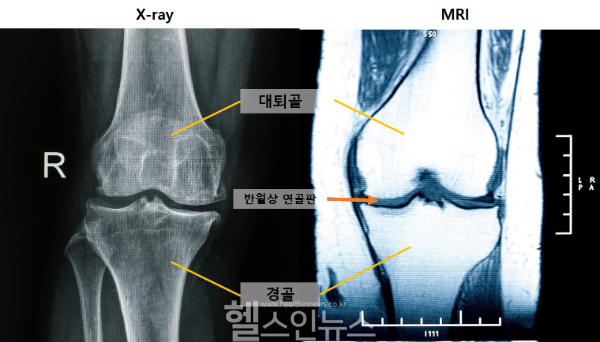

(왼쪽부터) 엑스레이 및 MRI 무릎 사진 (사진 제공=게티이미지뱅크)

[Hinews 하이뉴스] 무릎 관절염을 조기에 진단할 수 있는 새로운 MRI 지표가 국내 연구진에 의해 확인됐다. 엑스레이상 정상이더라도 MRI에서 ‘중앙 대퇴골 연골 손상’이 보이면 관절염 초기일 가능성이 높은 것으로 나타났다.

무릎 관절염은 연골과 관절 구조물이 서서히 손상되는 질환으로, 전 세계에서 많은 사람들이 앓고 있다. 그러나 초기에는 연부조직 손상만 있어 엑스레이로는 진단이 어렵고, MRI의 활용도가 상대적으로 낮아 조기 진단에 한계가 있었다.

연구 결과, 관절염이 진행되면서 MRI상에서 가장 먼저 관찰된 변화는 ‘중앙 대퇴골 연골 손상’이었다. 이 변화는 엑스레이상 관절염이 없는 0기 단계에서도 나타났으며, 조기 진단에 중요한 단서로 작용할 수 있음을 보여줬다.

또한 관절염 악화 위험을 예측하는 핵심 MRI 소견은 ‘내측 반월상 연골 돌출’이었다. 이는 시간이 지나면서 생긴 변화가 아니라, 구조적 이상이 관절염 진행에 큰 영향을 미친다는 것을 시사한다.

연구팀은 관절염 초기 MRI 소견과 관련된 엑스레이 지표도 분석했다. 엑스레이상 경골 골극, 내측 관절강 협착, 대퇴골 골극 순으로 나타났고, 모두 MRI에서의 연골 손상과 연관이 있었다.